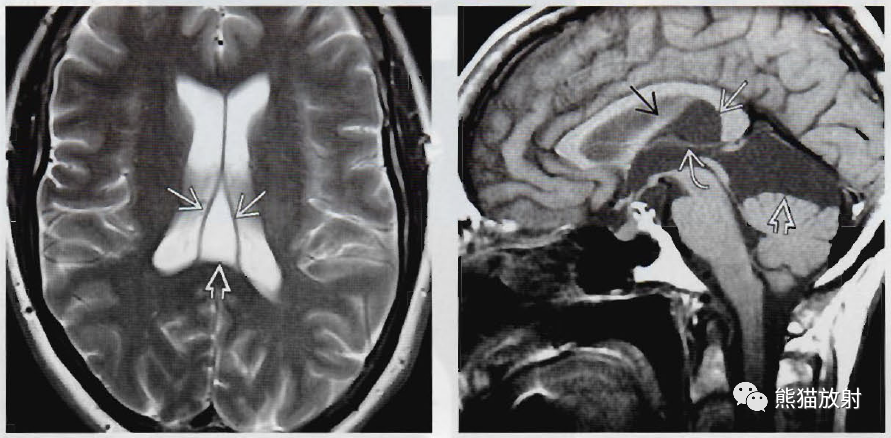

(左) 矢状位图和轴位插图显示中间帆腔。注意穹隆抬高、张开(空箭)。同时注意大脑内静脉和第三脑室向下移位(箭)。

(右) 40岁女性头痛,矢状位T1WI显示中间帆腔的脑脊液样扩张(弯箭),抬高穹隆(直箭),大脑内静脉平坦、下移(空箭)。该扩大的中间帆腔很可能与患者症状无关。

(左) 46岁女性头痛,轴位T2WI显示典型三角形脑脊液积聚(空箭),使穹隆向两侧张开(箭)。位于侧脑室后方是典型表现。

(右) 矢状位T1WI显示中间帆腔变异(白直箭),抬高穹隆(黑箭)、大脑内静脉平坦(弯箭),并且延伸至四叠体池和鞍上池(空箭)。该例很可能为中间帆腔蛛网膜囊肿。